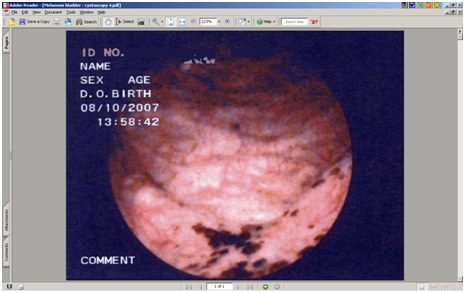

Clinical examination and radiological investigations including and ultrasound scan and a computerised axial tomogram scan (with intravenous contrast) of his urinary system were unremarkable. Routine blood tests including full blood count, urea, electrolytes and prostate specific antigen were normal. Urinalysis had revealed microscopic haematuria. There was no evidence of infection on urinalysis, mid-stream urine microscopy and culture. Urine cytology x 3 were normal. Flexible cystoscopy revealed several small, evenly pigmented, flat, brown/black lesions, measuring between 3 and 5mm in diameter, scattered throughout the bladder mucosa, with the greatest density and size of the lesions at the bladder base (Figure 1). Cold cup and subsequent resection biopsies were undertaken. There was no suggestion that the prostate could have been the source of his haematuria. Histopathology of both specimens showed many granules of golden brown pigment of varying size in the urothelial cells and within histiocytes in the underlying lamina propria (Figures 2&3).